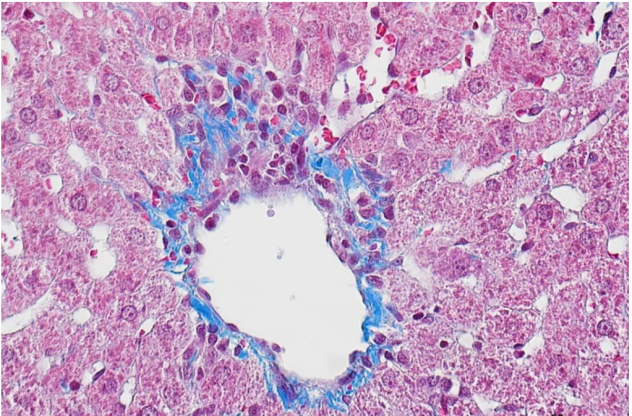

我們上期講過:MASSON染色,作為一種經典的結締組織染色方法,這種方法尤其適用于顯示并區分膠原、軟骨、黏液、肌纖維等組織成分。普拉特澤生物承接Masson(馬松)染色等病理染色相關服務上萬例,積累了操作大量經驗,為大家詳細分享馬松染色的實驗操作步驟與染色結果分析,同時為廣大科研工作者開展線上的理論培訓與線下實操,可承接染色實驗外包服務~下面將詳細介紹MASSON染色的專業步驟及相關技巧。

·無需水洗,直接使用苯胺藍或光綠液進行反染,使膠原纖維、粘液、軟骨等組織成分呈藍色或綠色。